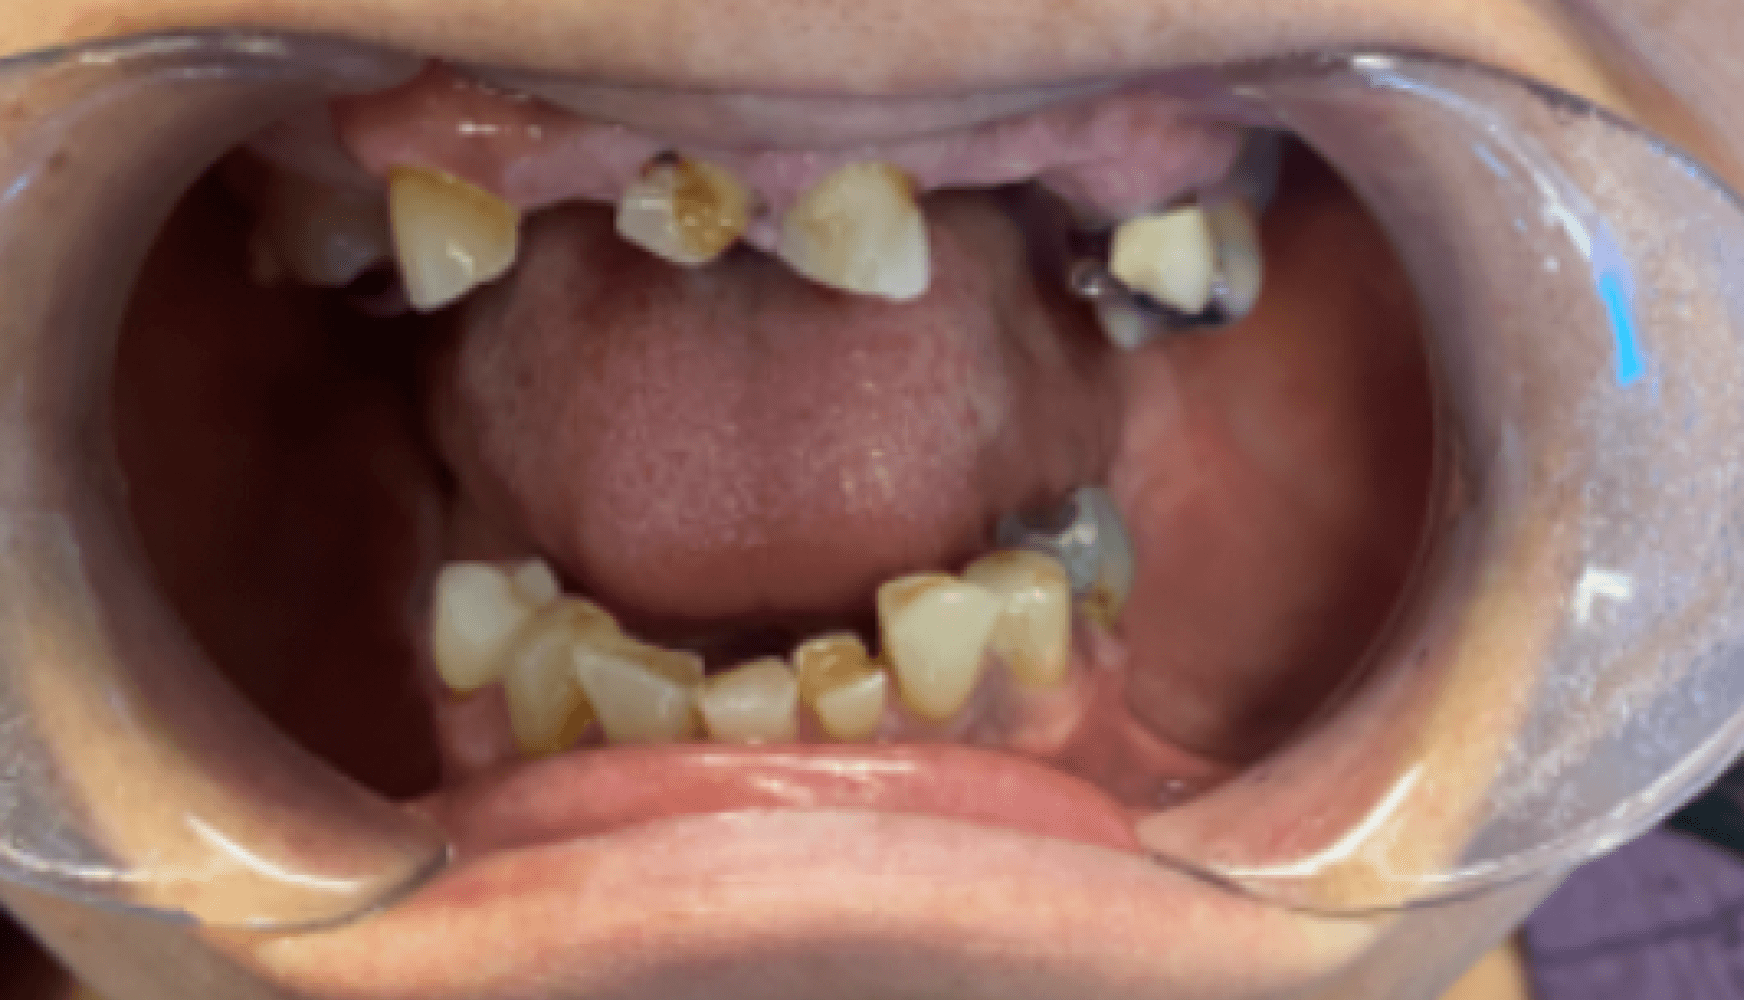

Fig. 1a, 1b, 1c, 1d: The patient’s dentition upon examination reveals significant reduction in VDO, a drastic left-to-right tilt in her smile line, and atrophy of the posterior mandibular ridge.

The patient presented with terminal dentition, multiple compromised and missing teeth, and a significant reduction in vertical dimension of occlusion (VDO) due to years of attrition and bruxism. The patient exhibited a drastic left-to-right tilt in her smile line, with significant atrophy of the posterior mandibular ridge. The right temporomandibular joint (TMJ) displayed a non-reducing disc and deviation to the right upon translation. These anatomical challenges, combined with the patient’s desire for improved function and aesthetics, necessitated a multi-phase treatment plan, beginning with immediate dentures and progressing to implant-supported dentures.